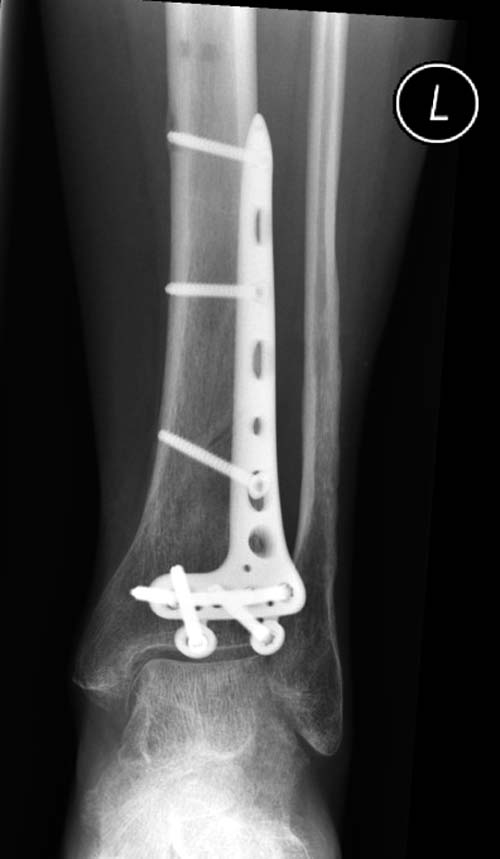

Первый случай, где перелом в результате падения с  небольшой высоты, где

мортиз рентген снимок показал отстутствие укорочения наружной

лодыжки и КТ срезы подсказали направления атаки. После такой фиксации

нет надобности в гипсовой повязке, брейс и через две недели движения в

суставе без нагрузки.